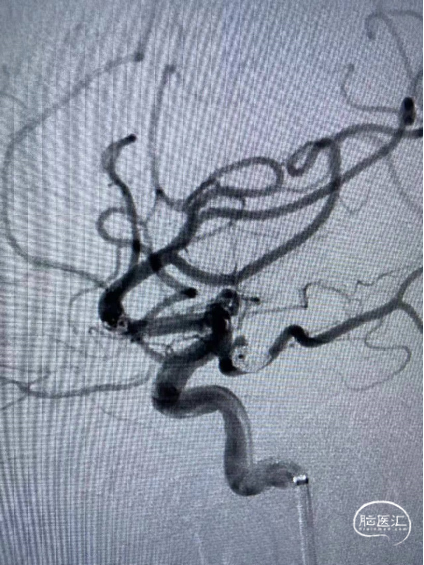

造影示支架位置满意,继续填塞强生ORBIT GALAXY 2mm×6cm弹簧圈,ev3 1mm×3cm,1mm×2cm弹簧圈,复查造影示动脉瘤栓塞致密,载瘤动脉通畅。

造影右侧颈内动脉、大脑前动脉、大脑中动脉显影良好。

术 后

![]()

替罗非班6ml/h持续泵入24小时后桥接双抗.

2022-2-12头颅CT复查:左侧基底节区腔隙灶、脑白质变性、脑萎缩、左额叶斑点状高密度影无著变,鞍区术后改变。